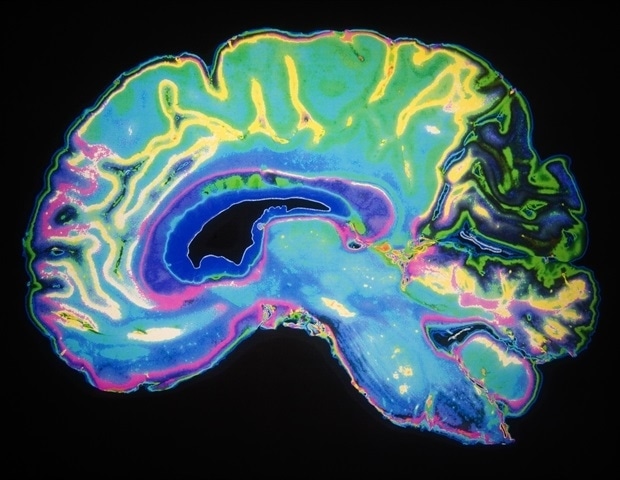

Ο ανθρώπινος εγκέφαλος ξεκινά τη ζωή του ως ένα μόνο κύτταρο. Στο τέλος της ανάπτυξής του, θα φιλοξενήσει ένα απίστευτα πολύπλοκο και ισχυρό δίκτυο περίπου 170 δισεκατομμυρίων κυττάρων. Αλλά πώς οργανώνεται αυτό το δίκτυο κατά τη διάρκεια της ανάπτυξης; Ερευνητές από το Cold Spring Harbor Laboratory έχουν αναπτύξει μια απροσδόκητα απλή απάντηση, που θα μπορούσε να έχει σημαντικές συνέπειες για τη βιολογία και την τεχνητή νοημοσύνη.